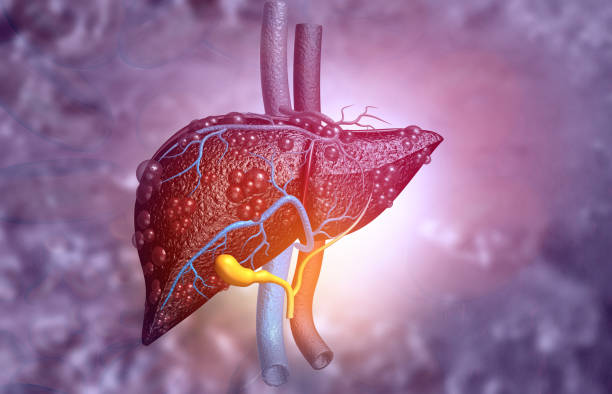

간경화 초기증상 10가지 총정리

간경화 초기증상은 증상이 나타나지 않거나, 미미한 증상만 나타나기 때문에, 무시하고 지나치기 쉬운 경우가 많습니다. 하지만, 이러한 초기 증상을 간과하면 질병이 진행되어 치료가 어려워질 수 있습니다. 따라서, 간경화 초기증상을 발견하면 적절한 검사와 치료를 받아 조기에 질병을 예방하고 치료할 수 있습니다. 따라서 이번 시간에는 간경화 초기증상에 대해 자세히 알아보도록 하겠습니다.